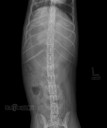

RadioQuiz 13 – Donnez-lui un petit sac

10 décembre 2012